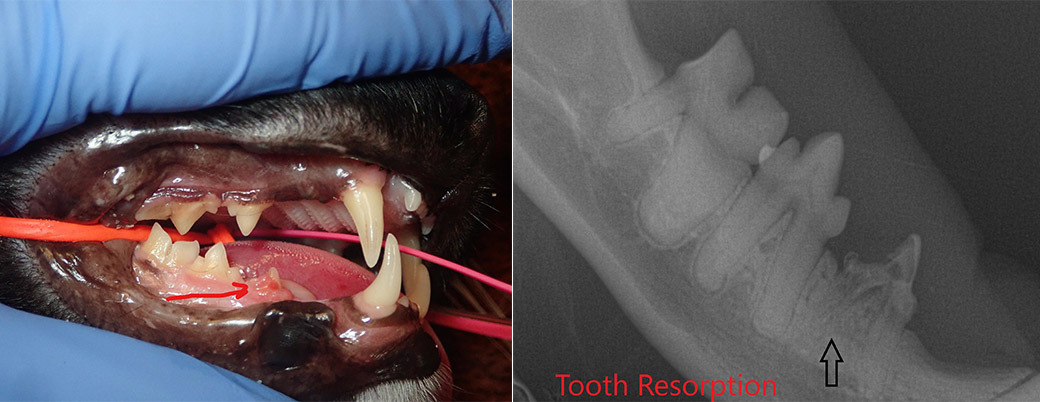

육안으로는 크게 문제가 없는것처럼 보이지만 실제로는 문제가 심각한 증례 사진 서베이 from google image